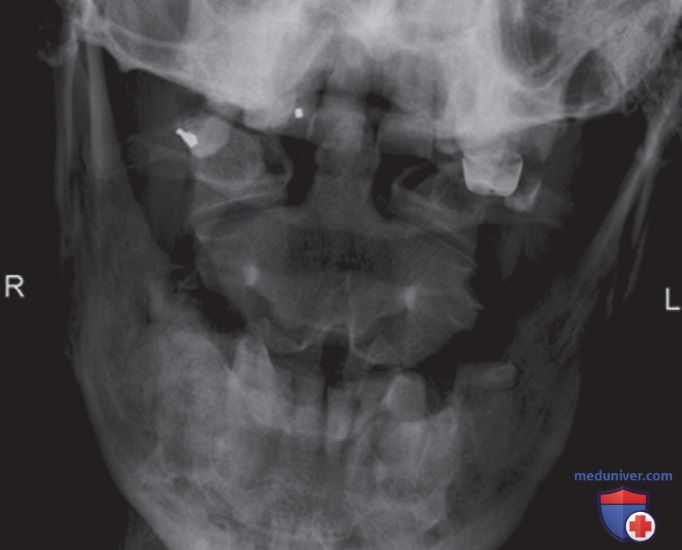

Рисунок 4. Рентгенограмма атланта и осевого позвонка в ПЗ проекции (с открытым ртом), полученная с использованием центральной камеры АКЭ.

• Не используйте АКЭ, если в непосредственной близости от ЗИ располагаются более толстые структуры, которые покрывают активированную ионизационную камеру (рис. 4)